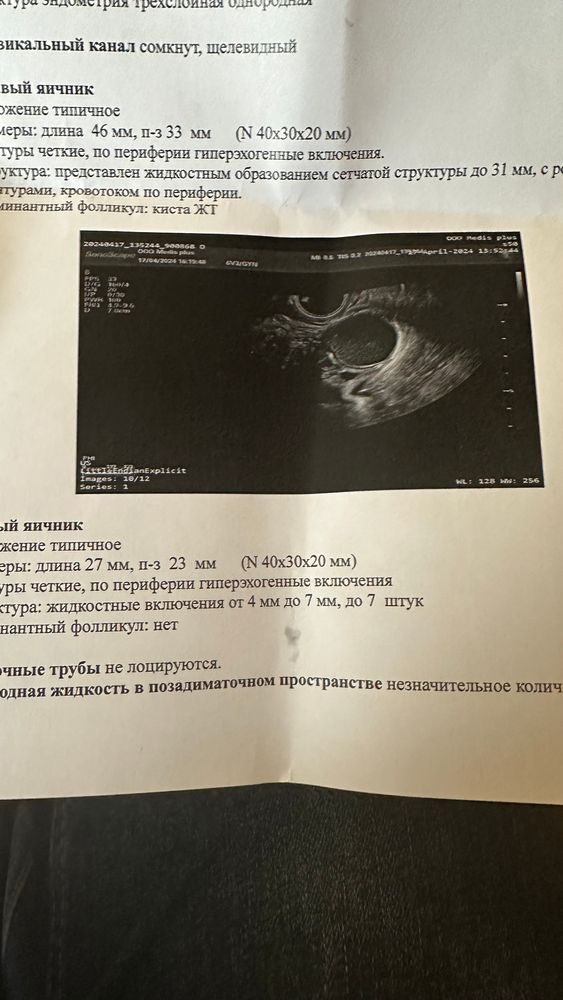

Вчера была на узи и врач поставил киста жт или эндомитриодная ?прописал вобэнзим и свечи индометацин.Кому прописывали такие препараты ?